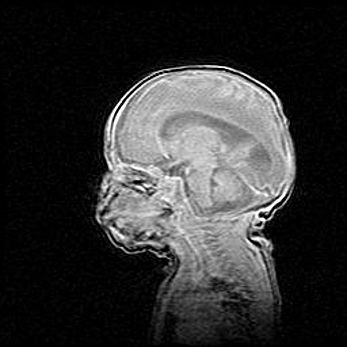

Мальформация Денди-Уокера. Киста задней черепной ямки.

Агенезия мозолистого тела.

Возраст: 2,5 месяца

Вес: 2420 г

Пол: женский

Окружность головы: 37 см

Срок гестации: 32 недели

Мальформация Денди—Уокера — редкий вид патологии ЦНС, представляющий собой врожденный порок развития каудального отдела ствола и червя мозжечка, ведущий к неполному раскрытию срединной (Мажанди) и латеральных (Лушка) апертур IV желудочка мозга. Для этогно синдрома характерна триада симптомов: гипотрофия червя мозжечка и/или полушарий мозжечка, кисты задней черепной ямки, гидроцефалия различной степени. В 70% случаев порок сочетается и с другими аномалиями головного мозга, в частности с агенезией мозолистого тела.